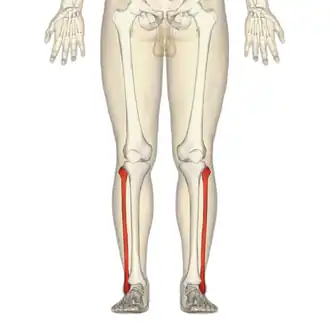

Fractura de peroné

La fractura de peroné es una fractura ósea que afecta al hueso homónimo situado en la pierna. Aunque puede presentarse de manera aislada, frecuentemente se asocia a fractura de tibia. Suele deberse a traumatismos importantes como caídas de altura, accidentes de tráfico o esguince de tobillo, en muchas ocasiones la fractura se produce durante la realización de la práctica deportiva. Raramente tiene lugar fractura de estrés del peroné, sin traumatismo previo, tras entrenamiento intensivo en el curso de grandes marchas o actividades atléticas.[1][2]

Dependiendo del sector del peroné, las fracturas de este hueso pueden asociarse a fractura de la meseta tibial o de la diáfisis tibial,[1] en la región del tobillo la fractura pueden presentarse de forma aislada o asociarse a fractura del maleolo tibial (fracura bimaleolar). La fractura del cuello del peroné asociada a lesión del tobillo se conoce como Fractura de Maisonneuve. Anatómicamente las fracturas de peroné pueden dividirse en los siguientes tipos:[1]